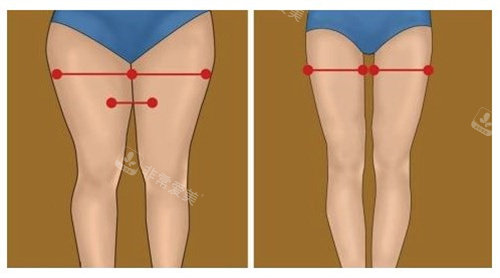

主治医生金院长在面诊时,用3D扫描技术生成了我腿部的三维模型,在屏幕上模拟出不同吸脂量对应的腿型变化,比较终确定右侧大腿抽取300ml、左侧280ml脂肪,小腿部分采用光纤溶脂技术。

针对我膝盖内侧的脂肪堆积,他计划采用微小切口技术;而小腿部分则结合肌肉放松术,改善我长期穿高跟鞋导致的肌肉紧张。

术后第五天去医院换药时,医生用超声波仪器检查了脂肪层厚度,显示两侧腿部的脂肪留存均匀,没有出现不对称的情况。